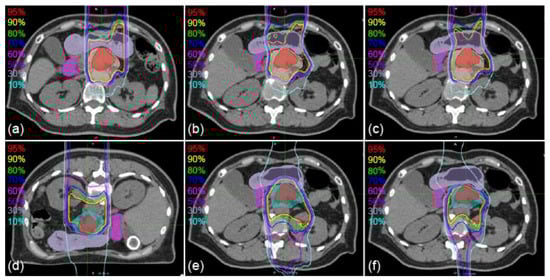

Figure 1. Sample axial images of supine and prone positions with delineated and transferred contours. (a) first irradiation day (1st-IRCT). (b,c) supine position CT images for treatment planning (SP-PlanCT) images. (d) 10th-IRCT images. (e,f) prone position (PR)-PlanCT images. Filled red, beige, cyan, mauve, and magenta regions show delineations of the gross tumor volume (GTV), clinical target volume 1 (CTV1), CTV2, stomach, and duodenum, respectively. Bold red, beige, mauve, and magenta regions show the GTV, CTV1, stomach, and duodenum transferred from the 1st-IRCT to SP-PlanCT images with intensity-based deformable image registration (iDIR) (b) and contour-based DIR (cDIR) (c). Bold red, cyan, mauve, and magenta regions show GTV, CTV2, stomach, and duodenum transferred from PR-PlanCT images to SP-PlanCT images with iDIR (e) and cDIR (f).